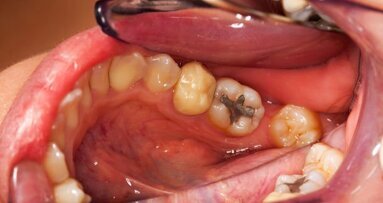

Conforme relatado pelo Dental Tribune International em janeiro, a proibição da UE sobre a amálgama levou a preocupações sobre problemas na cadeia de suprimentos no Reino Unido. O amálgama é o material mais comumente usado para obturações permanentes pelo National Health Service (NHS), de acordo com a British Dental Association (BDA). Como a Irlanda do Norte tem o maior número de dentes obturados proporcionalmente, o país teria sido a nação mais afetada do Reino Unido. Embora a BDA geralmente apoie a redução do amálgama, ela chamou a rápida eliminação do amálgama em práticas odontológicas de inviável e injustificável.